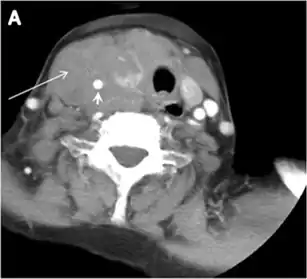

Thyroid nodules that are detected by an imaging study but have not been previously detected or suspected clinically are considered to be ITNs. ITNs are one of the most common incidental findings on neck imaging. ITNs are reported in up to 25% of chest CT scans, and in 16–18 % of cervical region cross-sectional imaging, including CT and MRI scans. The rate of malignancy in the detected ITNs on CT and MRI scans varies from 0% to 11%. Incidentally detected thyroid carcinomas are more likely to be papillary thyroid carcinomas (PTCs) (Fig. 3). Incidentally detected cancers tend to be smaller in size and less likely to have distant metastasis, as compared to clinically suspected thyroid cancers.[1]

Fig. 3. An incidental PTC in a 62-year-old male patient with lymphoma. a, b Enhanced axial CT scan and fused PET/CT scan of the neck demonstrate a well-defined, hypodense right thyroid nodule (white arrow) with high FDG uptake. The FDG-avid uptake in the left side (circle) is related to patient's known lymphoma, which resolved after treatment. c, d Transverse greyscale and sagittal colour Doppler ultrasound of the neck demonstrate a right thyroid irregular hypoechoic lesion with some micro-calcifications (white arrows) and increased vascularity.[1]

On CT scans, a malignant lesion is suspected when the margins are ill-defined and there is extra-thyroid extension, lymph node involvement, or invasion of the surrounding structures. The absence of these features does not exclude malignant tumours, especially papillary, follicular, and medullary thyroid carcinomas (Fig. 3). Therefore, ultrasound is the modality of choice for thyroid lesion evaluation, due to its superior spatial resolution compared to CT examinations. Sonographic features of malignancy are micro-calcifications, acoustic shadowing, anti-parallel orientation, marked hypoechogenicity, irregular or microlobulated margins, and increased vascularity. CT scans lack the ability to detect these reliable sonographic signs of malignancy. Therefore, further management of ITNs, if required, usually begins with thyroid ultrasound and FNA should be considered according to the ultrasound findings.[1]